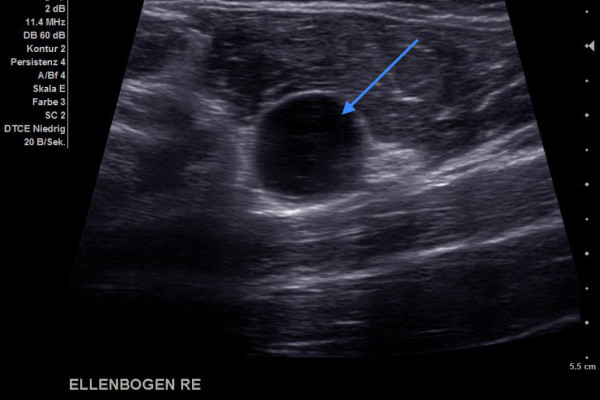

Diese Bild zeigt ein Gelenksganglion am Ellenbogen (Pfeil). Es sieht aus wie ein Ball und der Ultraschall geht komplett durch das Ganglion durch.